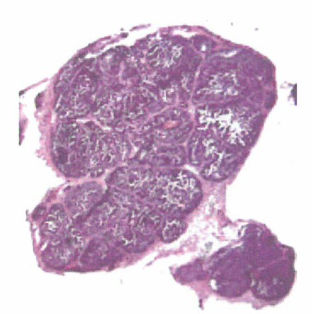

去美国看病中介机构爱诺美康介绍,肿瘤相关细胞分泌的基质金属蛋白酶,MMP主要由肿瘤基质中的炎症细胞和成纤维细胞产生。在MMTV-PyMT转棰因鼠的乳腺癌中,能够通过检测MMP裂解人工合成底物产生的荧光标记的聚阳离子脂质的能力而证明其存在。标记物能迁移罕邻近细胞会产生可检测的荧光信号。苏木素和伊红染色(左图)显示肿瘤被蛋白水解酶降解产生的光圈(右图),表明周围基质细胞参与蛋白水解酶产生。肿瘤能够降解胶原蛋白,它是基底膜的主要组成成分,能够通过裂解改变胶原IV底物使其产生绿色荧光而证明MMP的存在。在这个实验中,人乳腺癌细胞和成纤维细胞(红色)都具有较弱的胶原IV蛋D降解能力,但当这两种细胞共培养时,胶原IV(绿色)被裂解的区域更加明显,在成纤维细胞的区域尤为明显(黄色,红绿叠加为黄色)。当存在MMP抑制剂时,这种降解切割作用基本消失。